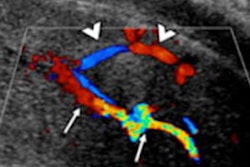

Superficial dorsal vein thrombosis. Color Doppler in transverse (A) and longitudinal (B) planes. The images show an absence of signal from the superficial dorsal vein of the penis and echogenic material related to thrombus (arrow). Presence of flow in the cavernous artery (arrowhead). All figures courtesy of Dr. Iñigo Zubiaguirre Telleria et al and European Society of Radiology (ESR) EPOS database.

Superficial dorsal vein thrombosis, or penile Mondor disease, is a benign and self-limiting process that affects sexually active men, especially during penile erection. It requires a clinical diagnosis (indurated cord on the dorsal aspect of the penis), but ultrasound helps to confirm the diagnosis and enables a follow-up to exclude a possible underlying tumor.

The treatment is conservative -- i.e., sexual rest and nonsteroidal anti-inflammatory medications -- and anticoagulation is not necessary, they noted.

Ultrasound findings include absence of flow and compressibility of the superficial dorsal vein of the penis. "It is possible to identify echogenic material within the vein that confirms the thrombus. In some cases, an increase in the caliber of the vein and inflammation of the adjacent soft tissues are observed," Telleria and colleagues stated.